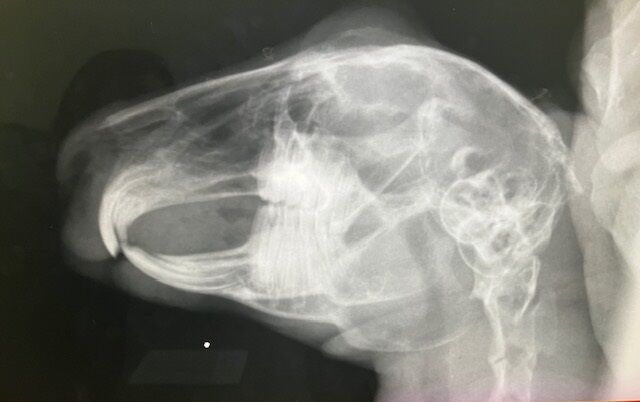

術前検査の血液検査、レントゲン、特に問題ありませんでした。

奥歯のチェックも問題なし。